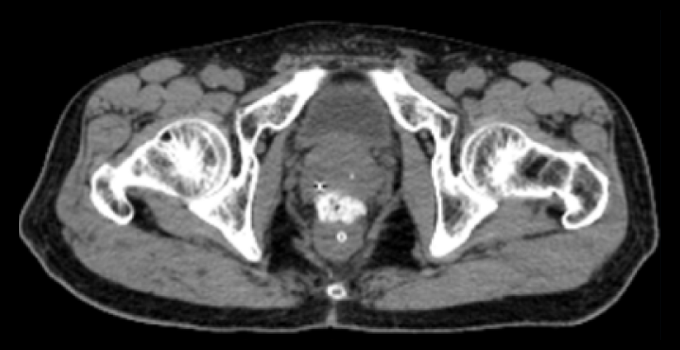

SpaceOAR Vue Hydrogel in different image modalities

kV Cone-beam CT image (first fraction).

kV Cone-beam Computed Tomography image (first fraction)*

kV Cone-beam Computed Tomography image (last fraction).

kV Cone-beam Computed Tomography image (last fraction)*

*Jeff Michalski, M.D. [2020]. Permission granted by Washington University Image.